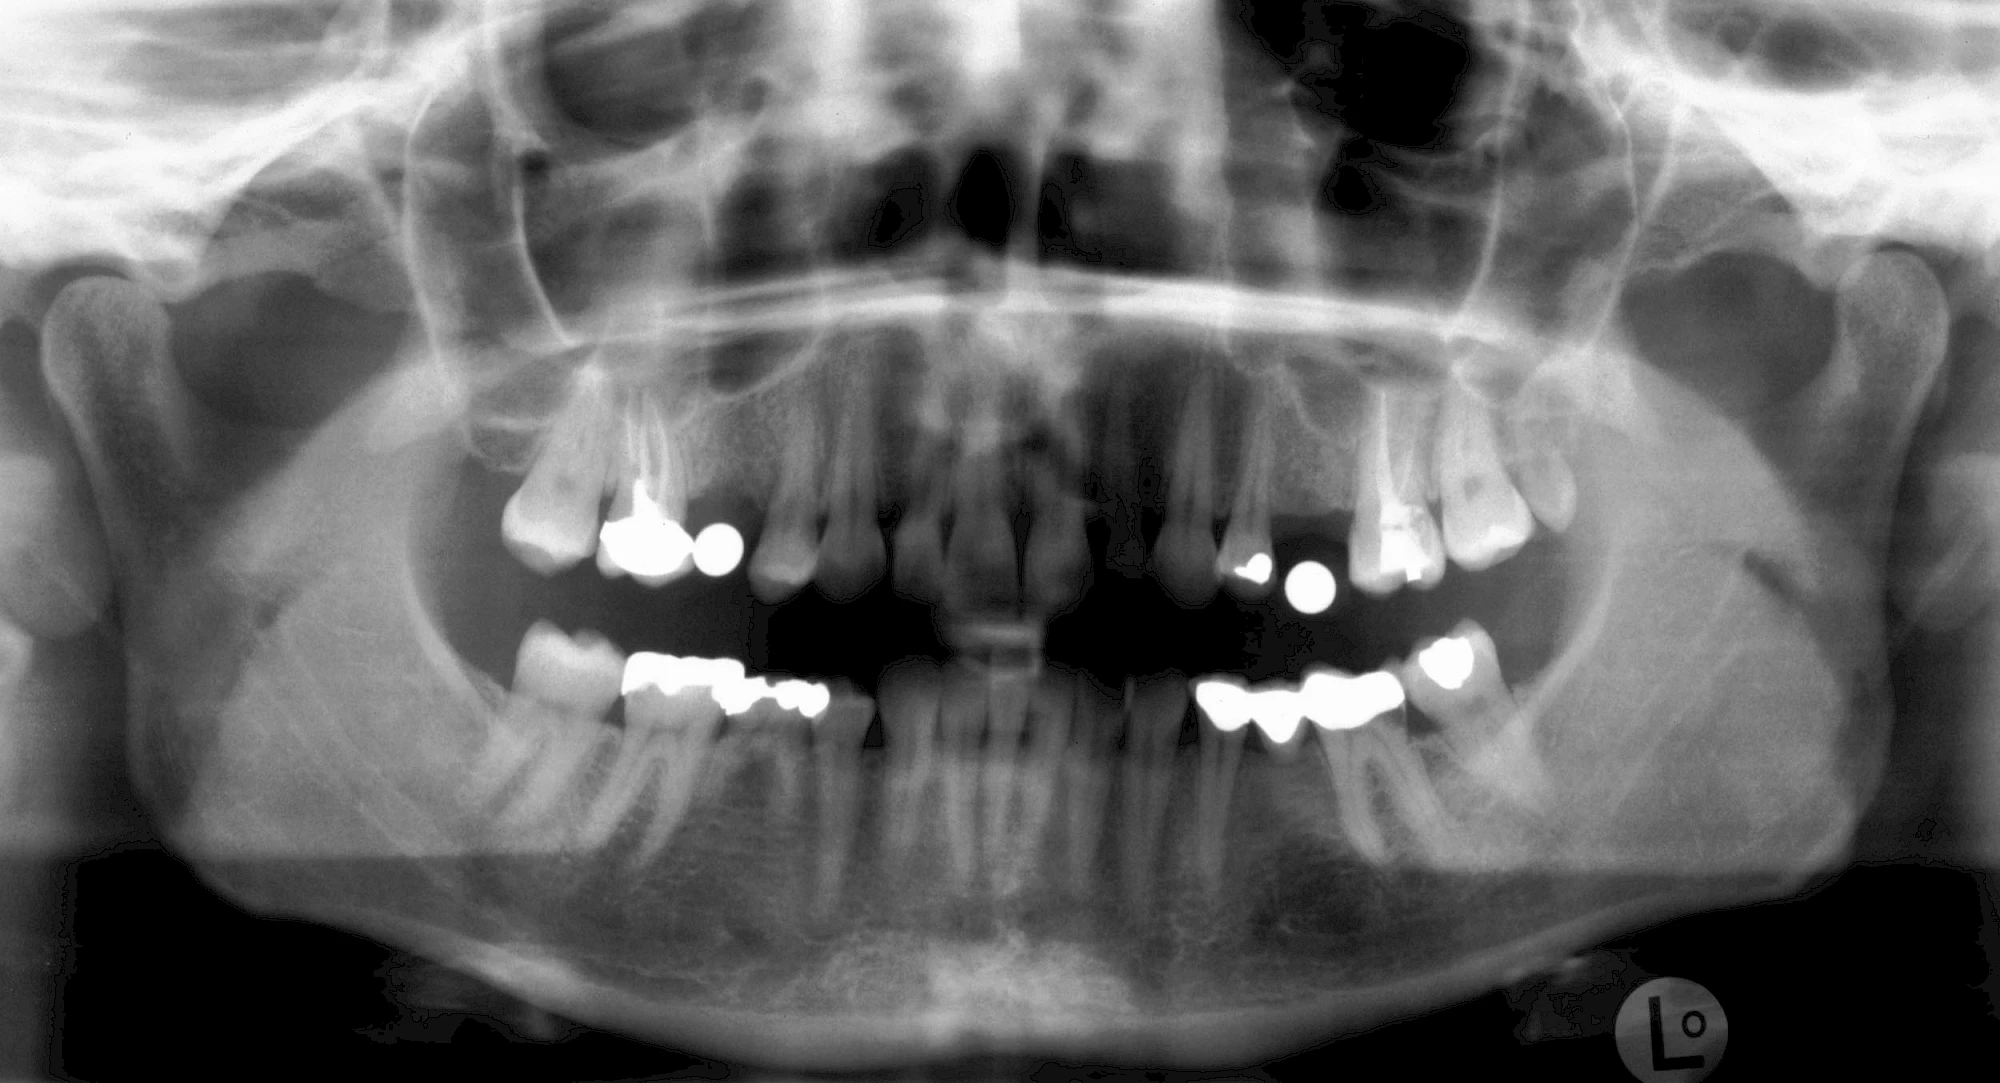

In diesen Fällen kann die Planung mittels verschieden aufwendiger Röntgen-Techniken (Übersichtsaufnahme, DVT) ggf. unter Zuhilfenahme speziell angefertigter Planungsschablonen sinnvoll sein.